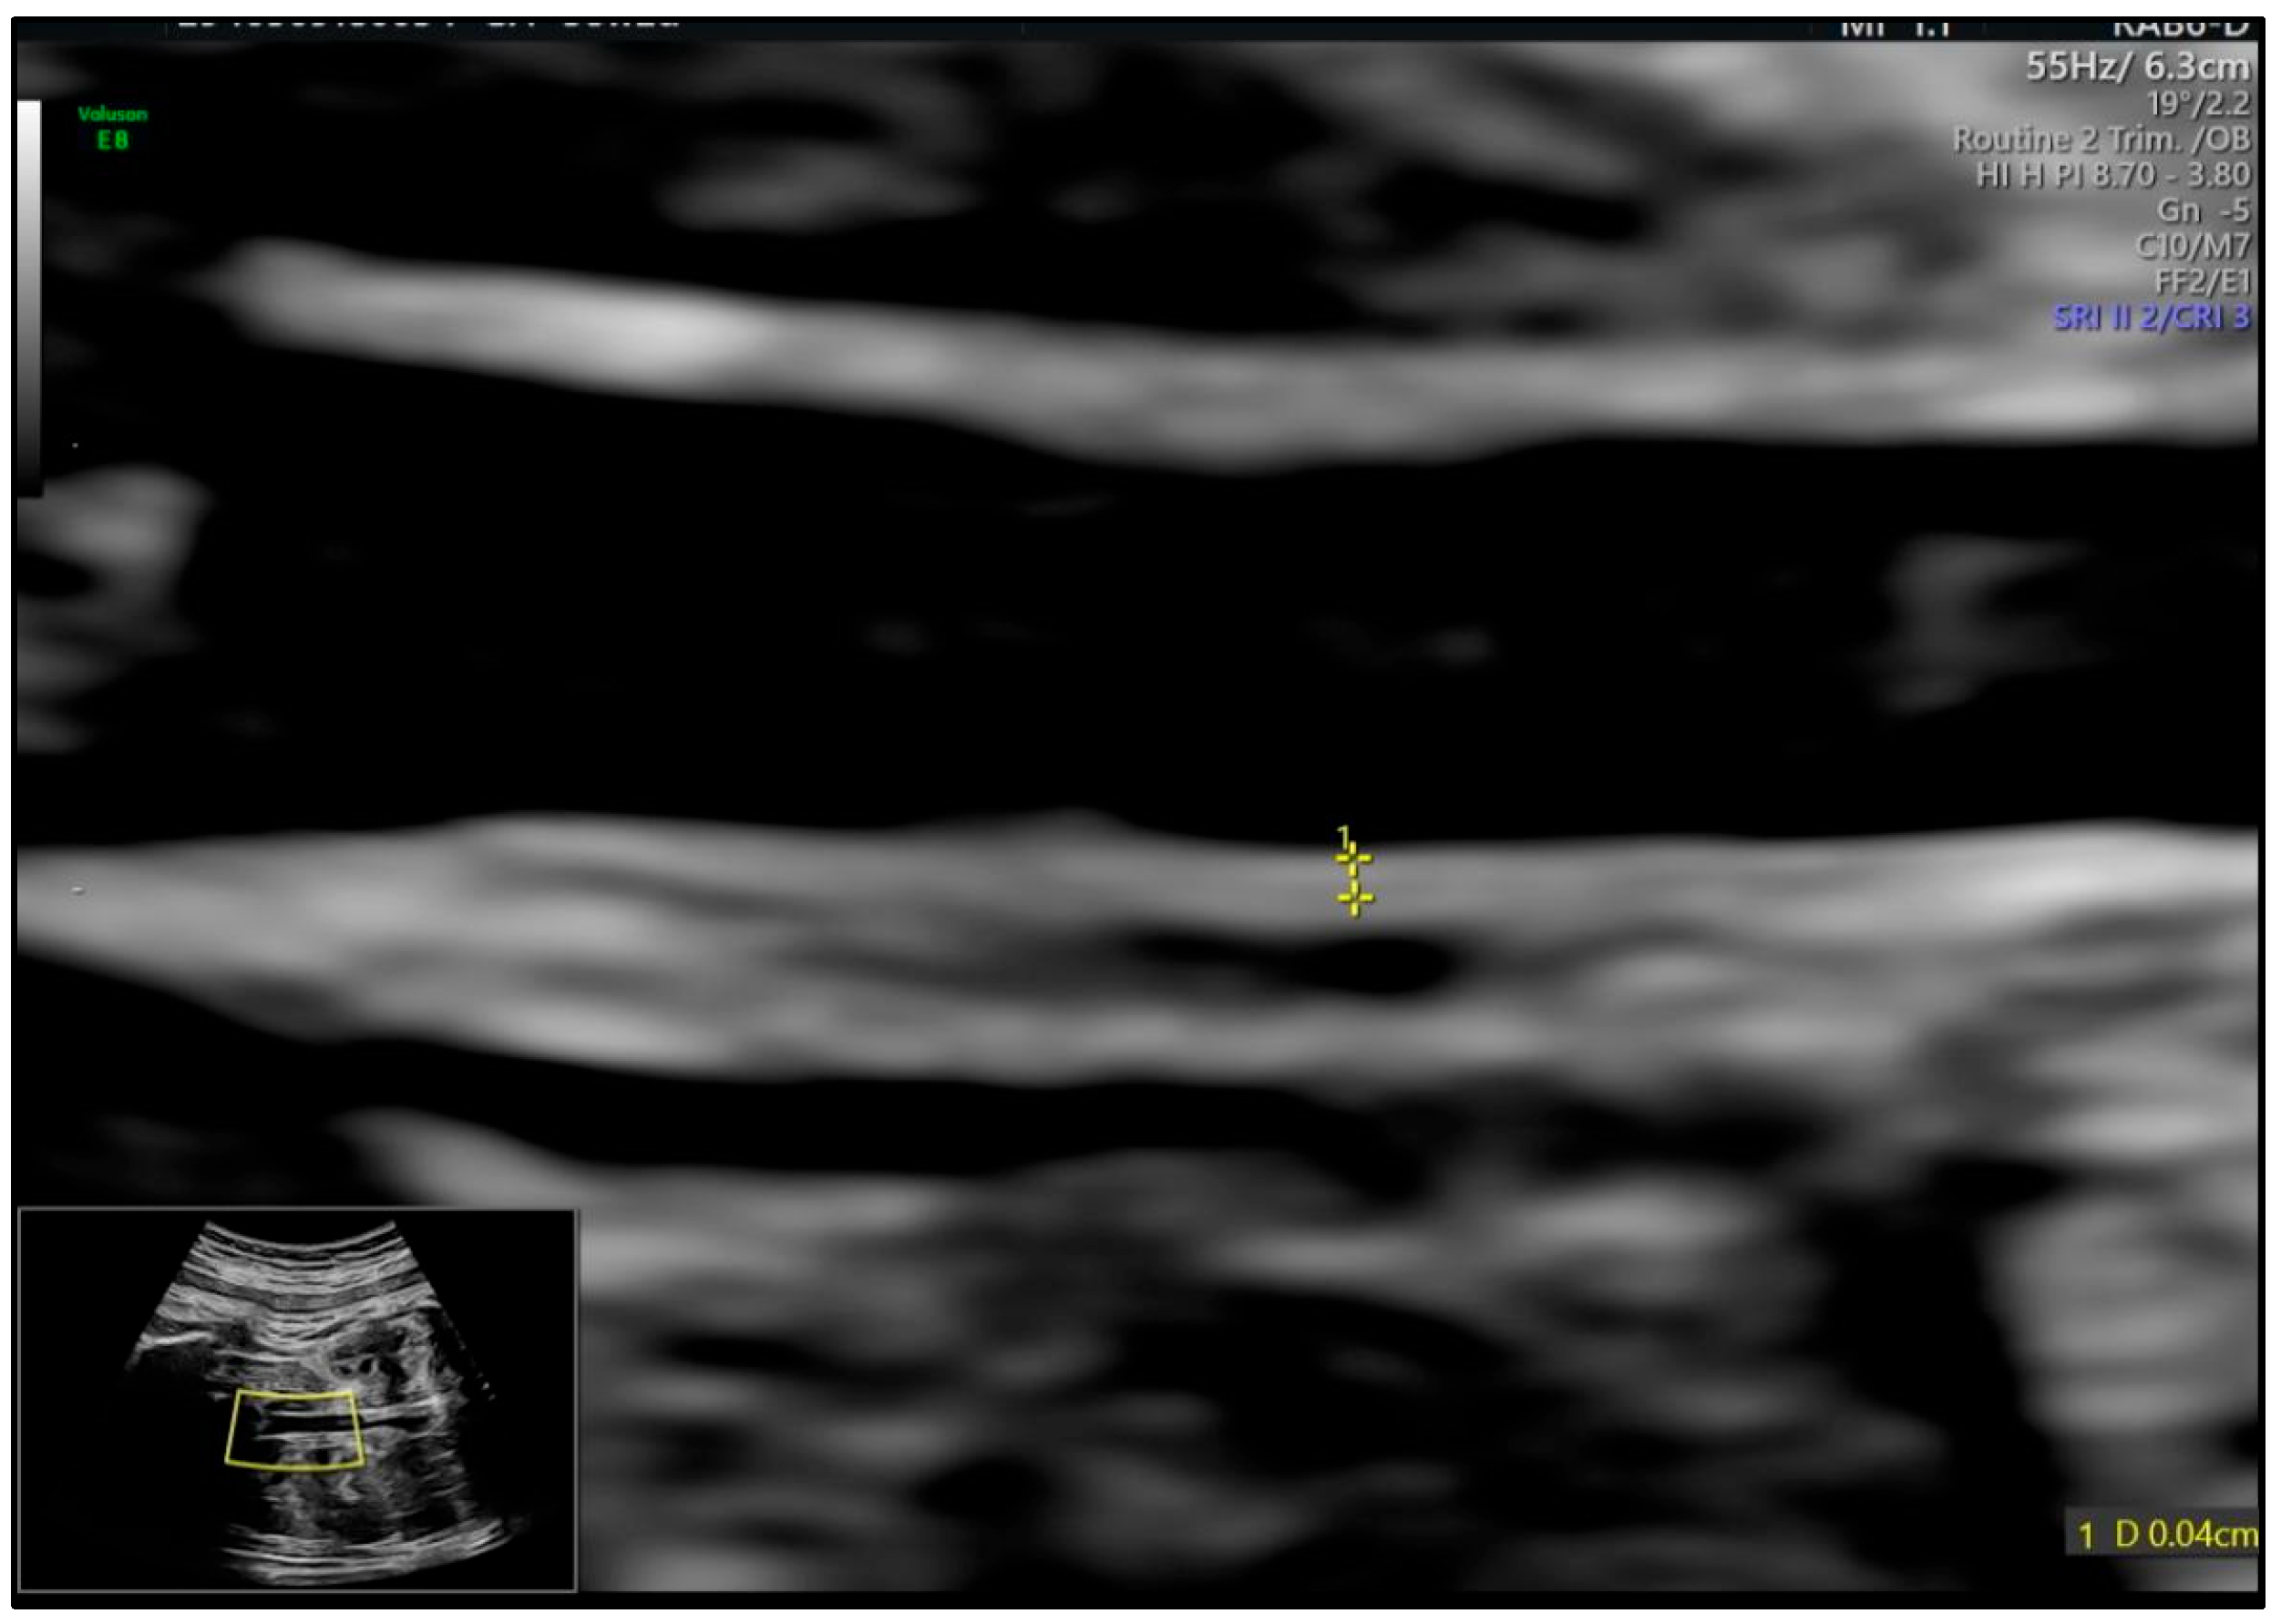

| Δ Abdominal-aorta IMT (mm) | +0.07 ± 0.03 | +0.11 ± 0.04 | +0.17 ± 0.05 | <0.001 |

| Δ fPWV (m/s) | +0.12 ± 0.14 | +0.29 ± 0.18 | +0.52 ± 0.21 | 0.001 |

| Δ TyG | 0.054 | 0.031–0.077 | <0.001 |

| Δ IL-6 (pg/mL) | 0.009 | 0.004–0.014 | 0.001 |

| Δ FMD (%) | −0.007 | −0.011–−0.003 | 0.002 |